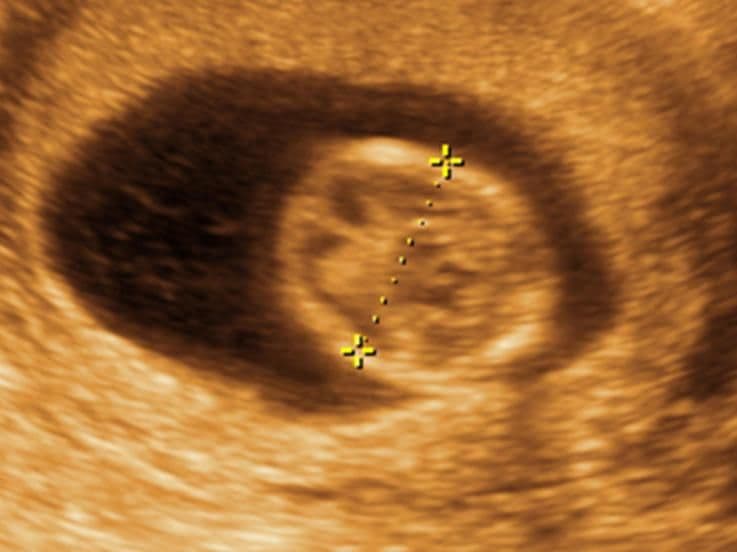

This scan shows a cross-section of your baby’s brain, with the two hemispheres clearly seen. From this point on, your baby’s brain measurement from one side to the other, taken just above the ear, is used as a reliable indicator of her growth and development.